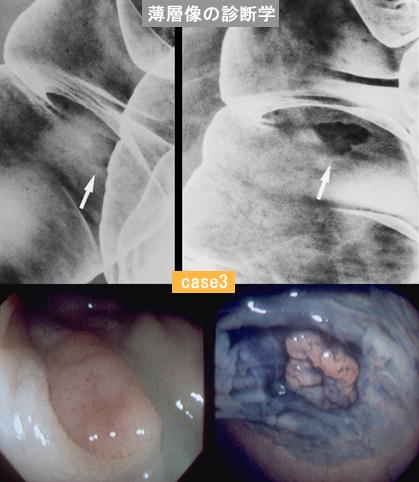

The important point in the X-ray reading of the colorectal cancer.

Large intestine(Colon)/Transverse colon

X-ray

10 - 14